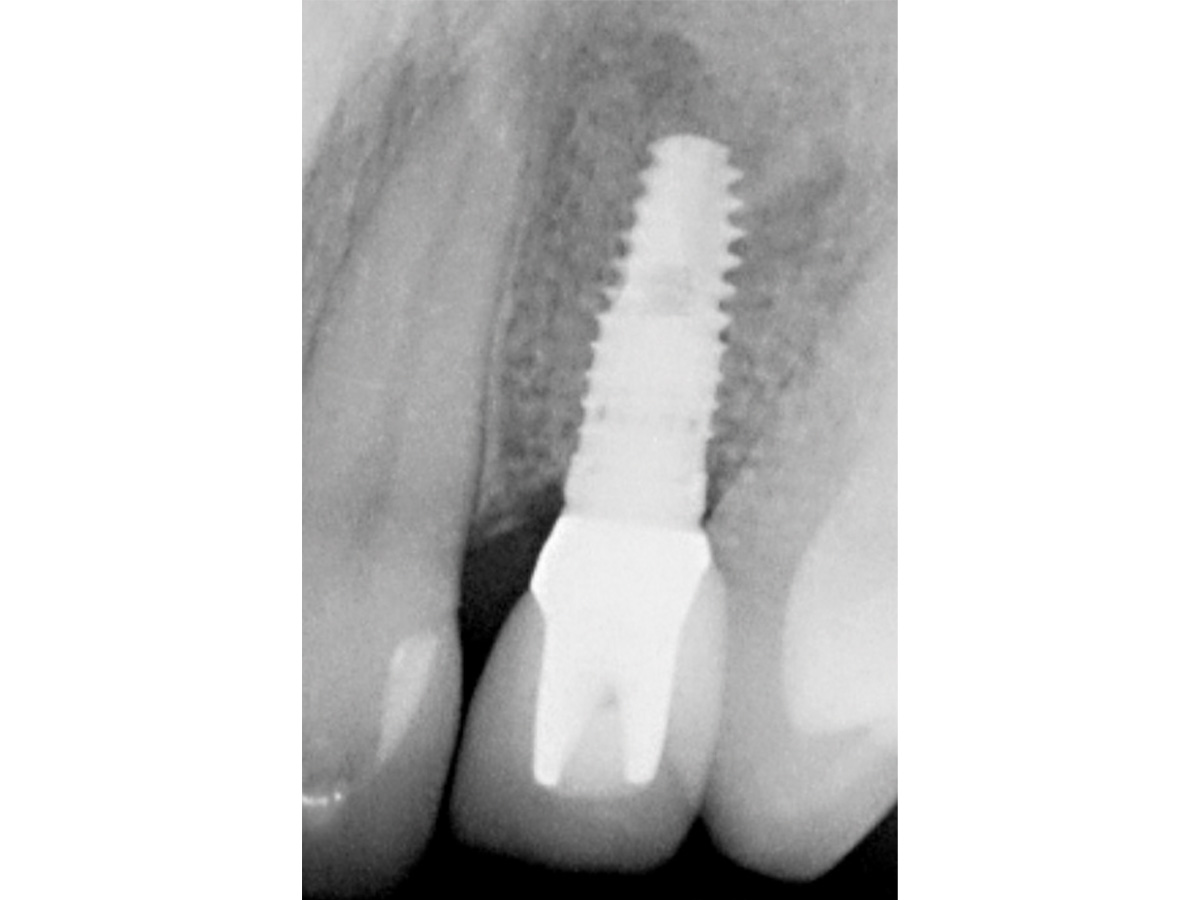

Abbildung 11

Ein Implantat mit 3,8 mm (Ø) konnte in seiner korrekten dreidimensionalen Position eingebracht werden.